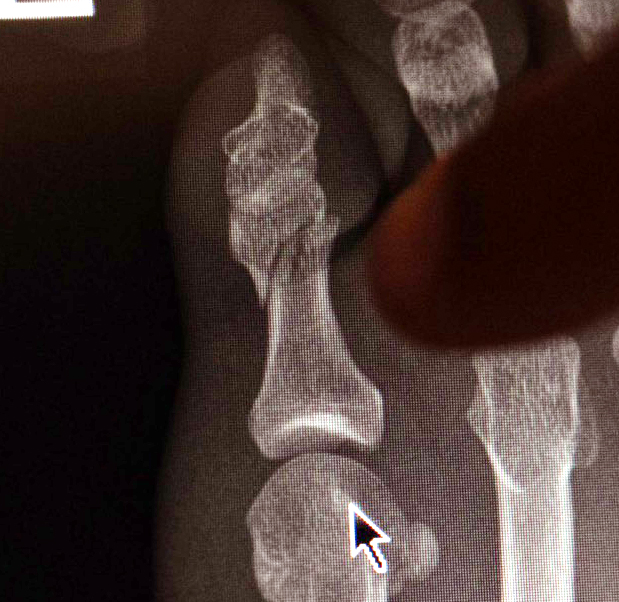

マクレガーが小指骨折で欠場を伝えるレントゲン写真(TheNotoriousMMA)